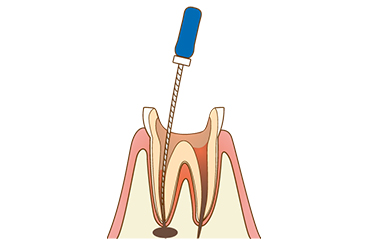

【1】感染部分を削る

虫歯菌が感染している組織を削って除去します。医師による目視のほか、歯科用CTなども活用します。

【2】神経の除去

感染した神経を露出させて除去します。根管内は細く複雑な形状をしているため専用器具を使用します。